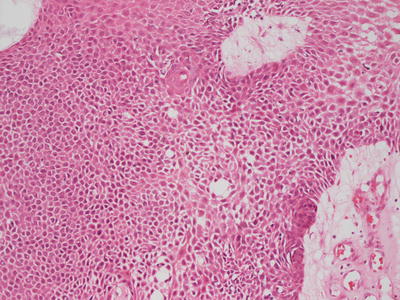

Fig. 24.12

Bland spindle cells course within focally myxoid stroma in myoepithelioma